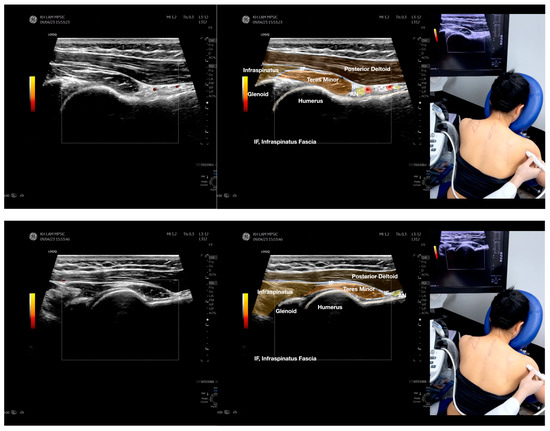

Figure 2.

Sonoanatomy of the lateral border of the inferior trapezius, its related muscles, and the infraspinatus fascia. The step-by-step scanning techniques of the structures illustrated in this figure have been shown in Video S6. Available online: https://www.dropbox.com/s/vjj49wiwdsidouz/Figure%202.docx?dl=0 (accessed on 1 January 2023). Dynamic ultrasound scanning of the anterior shoulder with the humerus externally rotated (palm up), elbow straight, and the shoulder actively flexed and abducted at about 90 to 100 degrees shows that the fibrotic and thickened bursa was noted to be snapping between the subscapularis tendon and the coracoacromial ligament, as shown in Video S3. The patient noticed this snapping during many of his daily activities with his shoulder flexed just above 90 degrees, e.g., taking off clothes and combing hair. Ultrasound-guided injection of the thickened and fibrotic bursa did not reproduce the usual pain nor reduce the pain, and it did not improve the shoulder snapping and flexion power with the elbow straight, shoulder flexed to 90°, and the humerus externally rotated (palm up). Ultrasound-guided injection of the cortical break reproduced the concordant pain and temporarily and partially reduced the pain with snapping and residual anterior shoulder pain (Video S4), but it did not change the snapping or weakness in the right shoulder flexion with the humerus in external rotation. With the failure of direct anterior treatment to the suspected lesions, it was essential to further explore other causes for the anterior painful snapping. Further detailed musculoskeletal examination of the scapular movement showed that the right scapulothoracic movements were not smooth compared to the left counterpart (Video S5) [4,5]. There might be some disruptions in the right infraspinatus fascia (IF) and its related muscles, including the lateral edge of the right inferior trapezius, rhomboid minor and major [6], teres major, latissimus dorsi [7,8] (LD), and posterior deltoid attachments to the IF [9,10]. Clinically, prominent and active trigger points were observed in the right infraspinatus muscle. Holding the inferior angle of the scapula, with the examiner’s fingers, especially over the origin of the teres major muscle over the scapula, the latissimus dorsi [11,12,13] and the scapular insertion of the rhomboid major muscle significantly improved the power of the resisted shoulder flexion with the elbow straight and the shoulder flexed to 90° with the humerus externally rotated (palm up). In order to illustrate the utilization of ultrasound-guided sonopalpation and ultrasound-guided digital palpation for detecting the suspected lesions of the IF and its related muscles, we presented the following videos (Videos S6–S9) and still images (Figure 2, Figure 3, Figure 4 and Figure 5) to demonstrate the essential techniques and crucial points of getting the normal sonoanatomy of the IF and its related structures. The gross anatomy of the IF and its related muscles were also shown in Figure 6, Figure 7 and Figure 8.